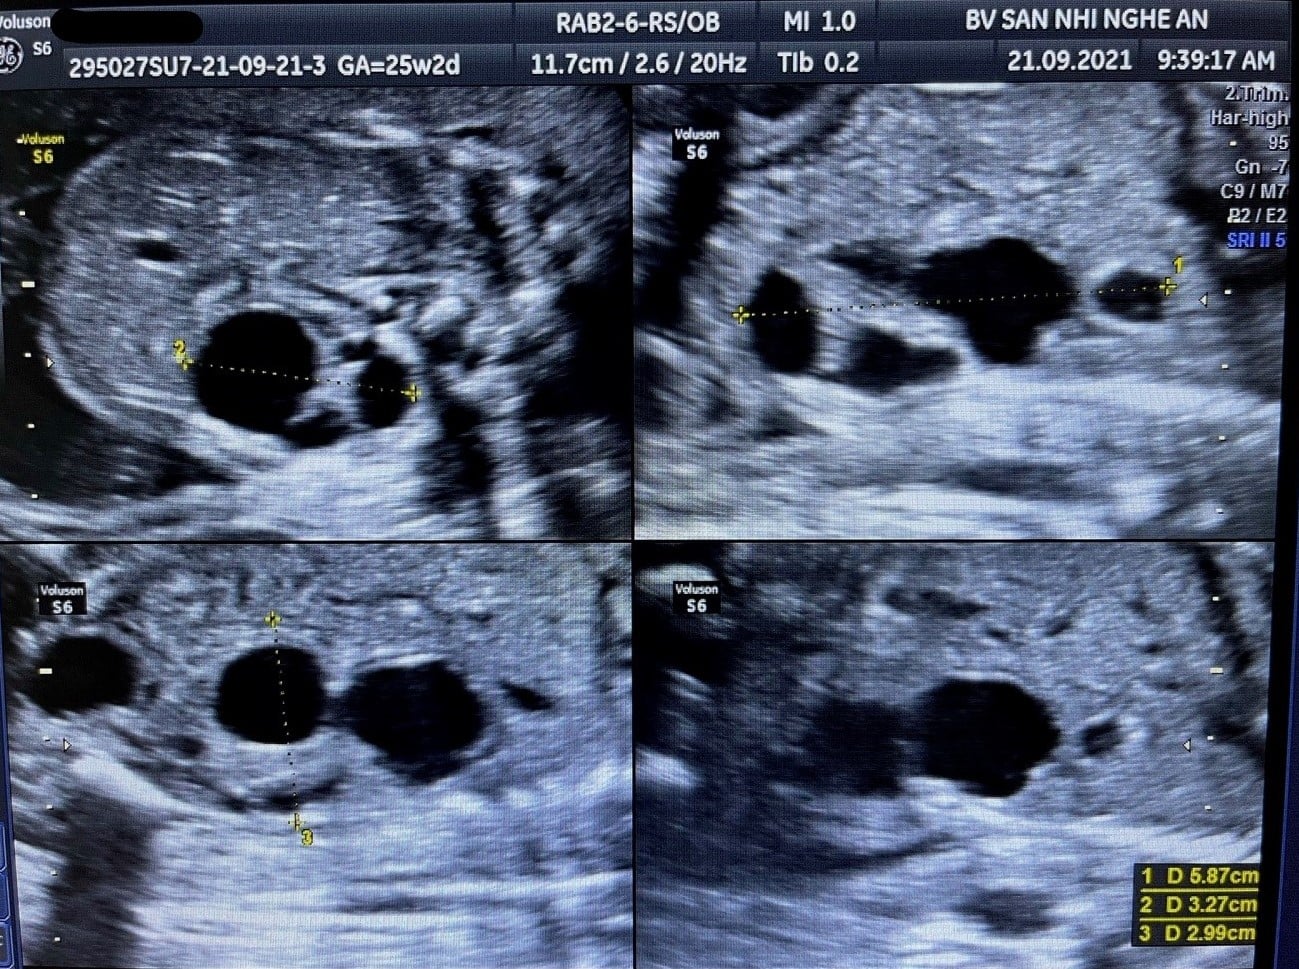

Trường hợp thai phụ 24 tuổi, mang thai lần đầu, không có tiền sử bệnh lý, kết quả sàng lọc 12 tuần chưa thấy bất thường, siêu âm thai lần đầu tại Trung tâm sàng lọc chẩn đoán trước sinh và sơ sinh – Bệnh viện Sản Nhi Nghệ An phát hiện bất thường thận. Được chẩn đoán loạn sản thận đa nang (Multicystic Dysplastic Kidney-MCDK) thận trái, tình trạng ối bình thường, không có bất thường khác kèm theo. Sau khi thăm khám và tư vấn, thai phụ và chồng quyết định tiếp tục theo dõi thai kỳ.

Hình ảnh siêu âm: Thận bị ảnh hưởng có hình ảnh giống một khối u nằm cạnh cột sống với nhiều nang kích thước khác nhau. Không thấy cấu trúc nhu mô thận bình thường. Nếu bị cả hai bên thận, sẽ gây thiểu ối nặng.